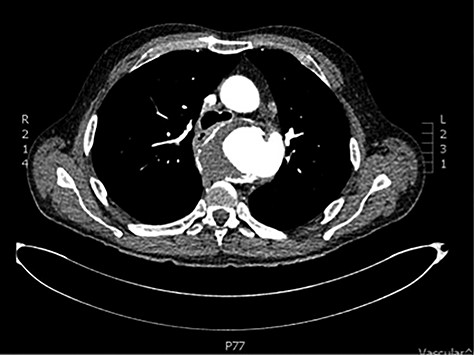

The patient was transferred and stabilized on the critical care unit and discussed with the interventional radiologist. In conjunction with the interventional radiologist and cardiothoracic teams, the patient underwent radiological stenting of the large aneurysm with TEVAR procedure (Figs 2 and 3). Following the procedure, the patient continued to have large volume haematemesis and melaena and underwent repeat oesophago-gastro-duodenoscopy which demonstrated large amount of blood and clot in the distal oesophagus and stomach with continuous brisk active arterial bleeding at approximately 40 cm, which was unsuitable for any endoscopic therapy. Follow-up CT angiography demonstrated satisfactory appearances of the thoracic aortic stent graft with no evidence of endo-leak. The left subclavian artery was well opacified, and the excluded aneurysm sac contained multiple locules of gas suspicious of ongoing fistulous communication with the oesophagus. Following further stabilization, the patient underwent repeat procedure with identification of a tear in the lower third of the oesophagus. The patient was subsequently managed as an oesophageal perforation with no fluid or oral intake and was commenced on peripheral total parenteral nutrition prior to definitive primary repair.

CT scan demonstrating patent stent with no suggestion of endoleak and lack of contrast in aneurysm sac.